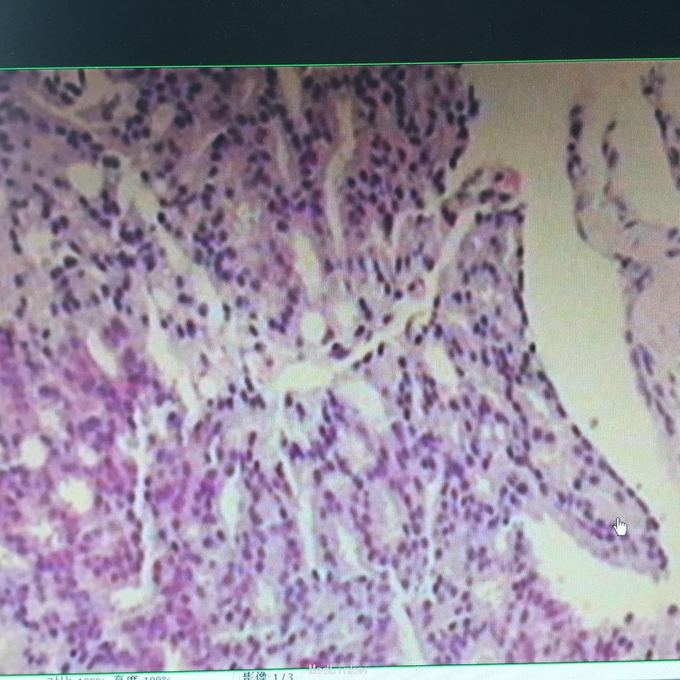

total PSA>100;前列腺磁共振平扫示:前列腺外周带左后方肿块,DWIBS信号明显增浓,考虑前列腺Ca。 行会阴前列腺穿刺活检术,病理示:前列腺腺癌。 全身骨扫描示:超级骨显像,符合前列腺Ca并多发骨转移。